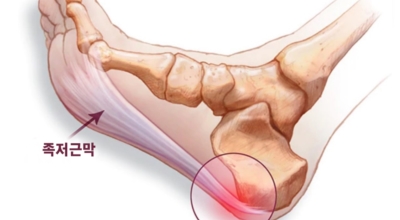

족저 근막이란 발가락 시작지점부터 발뒤꿈치뼈까지 발바닥 전체를 감싸고 있는 두꺼운 막을 말해요. 족저 근막은 발바닥 아치를 지속시켜 발바닥이 지면을 내딛음으로써 나타나는 충격을 흡수하는 중요한 역할을 수행하고 있어요. 이 족저 근막에 일차적으로 서서히 조직 손상이 일어나고 계속적인 활동으로 인해 염증이 커지면서 발 뒤꿈치 부근 통증을 유발하게 되는데 염증은 무리하고 반복적인 동작, 과도한 사용으로 마찰에 의해 발생해요.

주요 증상은 통증으로 발뒤꿈치 안쪽이 아주 아프며, 맨발로 바닥을 걸을 때 걸음을 내딛을 때마다 통증이 있어요. 가장 심한 통증은 아침에 일어나 첫 걸음을 뗄 때인데, 밤에 족저근막이 수축하다가 발에 체중이 가해지면서 갑자기 늘어나는 현상입니다.